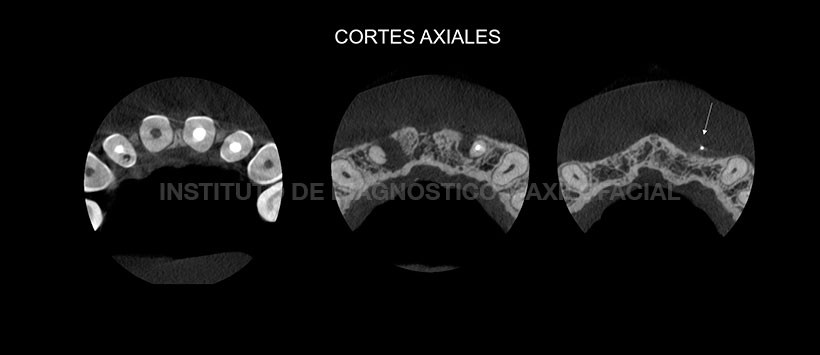

A la evaluación de la tomografía de campo pequeño, se confirma que la pieza 22 presenta una sobreobturacion pero se encuentra orientada hacia vestibular comprometiendo tejido oseo y blando. Así mismo el proceso osteolitico previamente descrito esta localizado en mesial, comprometiendo hueso medular y  tabla osea vestibular. (Figura 2, Figura3, Figura 4)

En las reconstrucciones 3D se evidencia de manera ilustrativa la orientación de la sobreobturacion de la pieza 22 así como la extension y repercusión del proceso osteolitico apical.